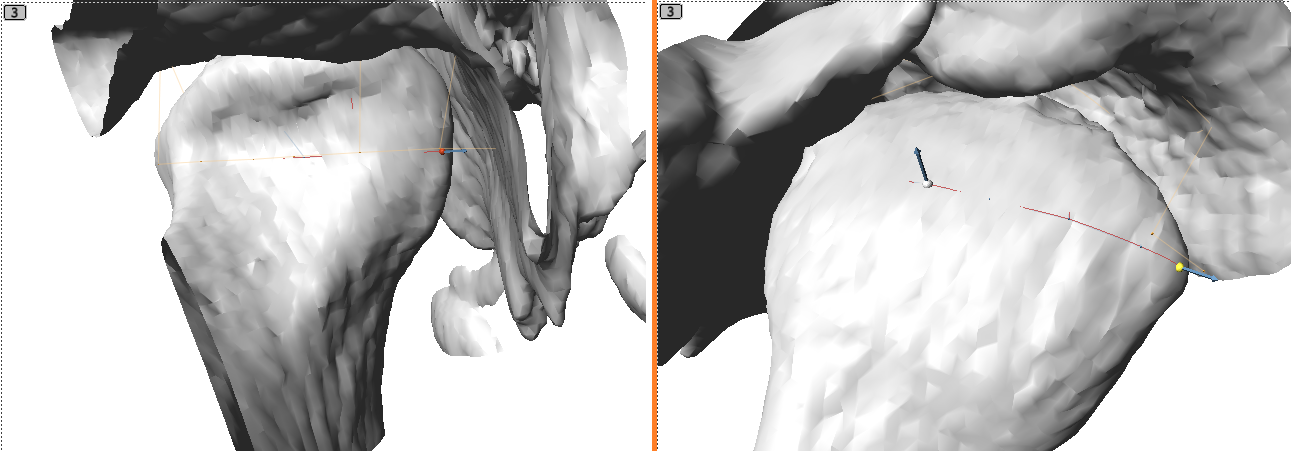

Placing the Joint Primitive

- Load the exported volume.

- In the surface tab, select an iso value that produces surfaces without holes in the condyle and fossa.

- Click the

button, then hold ‘shift’ and left click on the condyle to add the joint primitive. - Move the red and yellow control points to the medial and lateral sides of the condyle.

- Optionally, to restrict the condyle white point to a plane that keeps this point equidistance from the lateral points, first, right click in the 3D or any slice window to bring up the pop menu and select “Align Avatar to:” -> “Joints” -> ‘Joint’. This aligns the avatar to the joint, placing it at the midpoint between the lateral red and yellow points and aligning the sagittal slice perpendicular to the lateral points. Next, right click on the joint’s overlay button and select the “Snap condyle white landmark to sagittal slice” command, which projects the condyle white point to the sagittal slice defined by the avatar and also selects the condyle white point. Finally, use the sagittal slice window to move the condyle white point.

Adjusting the Joint Primitive

- In the landmarks tab, select the joint primitive.

- Set the name and dimensions.

- Toggle the volume or surface with the

or

buttons to verify that the top of the patch is on the top of the condyle. If the patch is upside down, then click the “Upside Down” button under “Direction”. - Use the “Flip” button to swap the point ordering, which is seen with the swapped yellow and red control point positions. This example places the yellow point on the lateral condyle position and the red point on the medial condyle position.